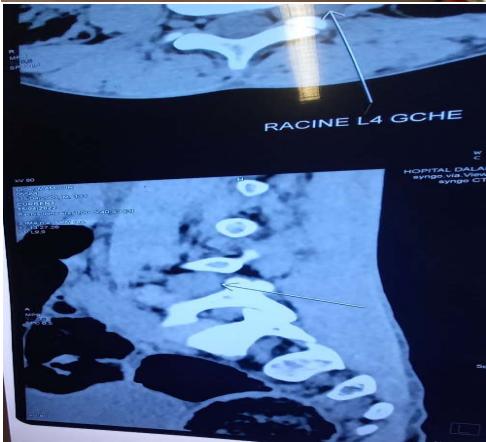

CT lumbar spine

Hypertrophy of the left L4 root of $12.8 \, \text{mm}$ in probable conflict with the disc which could evoke neurofibromatosis.

The scanner revealed hypertrophy of the left L4 root of $12.8 \, \text{mm}$ in probable conflict with the disc